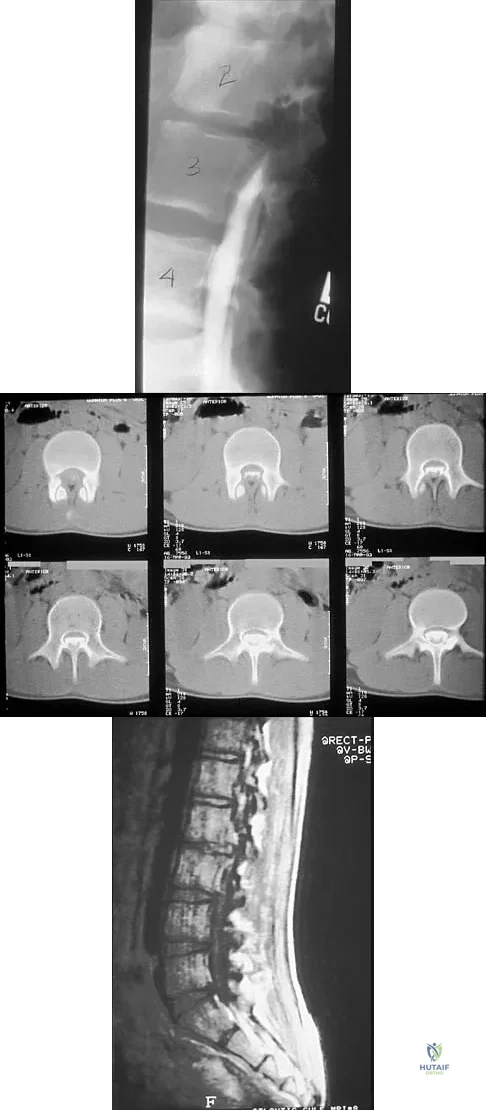

A 14-year-old football player has had thigh pain and weakness following a full-contact scrimmage 24 hours ago. He recalls that he felt a sharp pain in his back after colliding with a much heavier player. Examination reveals that the spine is minimally tender to palpation in the upper lumbar region. Motor testing reveals quadriceps weakness bilaterally, and a reverse straight leg raising test is positive. Plain radiographs of the thoracolumbar spine are normal. A myelogram, a CT scan with contrast, and an MRI scan are shown in Figures 41a through 41c. What is the most likely diagnosis?

Explanation

Figure 12 shows the lumbar CT scan of a 24-year-old man who was injured in a snowmobile accident. What is the mechanism of injury?

Explanation